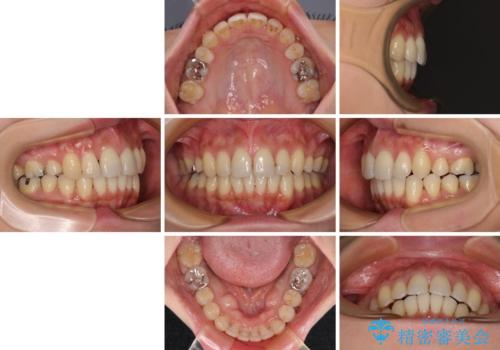

上顎前歯の突出を軽減 インビザラインによる抜歯矯正

- 上の前歯の突出感を気にして来院された患者様です。

目立たない装置を希望とのことで、上顎左右第一小臼歯を抜歯し、インビザラインにて矯正治療を行うこととしました。

インビザラインにて抜歯矯正を行うと、高頻度で奥歯が咬み合わなくなります。

また、抜歯スペースに向けて奥歯が移動する際、必ず傾斜して移動するため、仕上がりの咬み合わせはワイヤー矯正と比べて明らかに劣ります。

抜歯スペースが閉じてからも咬みにくさ改善のためマウスピース矯正を継続するため、治療期間は長期化します。